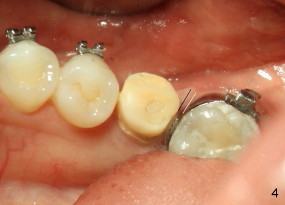

The tooth #19 has been lost for 8 years with tilting of #18 (black line in Fig.1). A 6x8 mm Bicon implant (3 mm post) was placed as distal as possible (I in Fig.2). Three months later, the implant was uncovered with evidence of osteointegration (arrowheads in Fig.3). A 4x6.5 mm 0 degree non-shouldered abutment with 3 mm post (A) was inserted into the implant well. The flat surface of the abutment needed to face distal in order to seat the abutment without interference. The implant/abutment complex was used as an anchorage to upright #18. The tooth #17 was extracted prior to orthodontic treatment (compare Fig.5,6 vs. 1-3). A bracket was bonded to Jet temporary crown of #19 and open coil spring was placed between #18 and 19. In the first two months, distalization of #18 is limited (between black and white lines in Fig.4), partially due to the fact that the bracket of #19 was debonded quite easily. A premolar band (B in Fig.5) was cemented to the temporary crown of #19. In another two months, the tooth #18 was pushed to desired position (arrowhead) under the tension of open coil spring (*). The mesial crest height of #18 was increased during uprighting (arrow, as compared to Fig.1-3). A new temporary crown was fabricated to fit the enlarged space of #19 with cementation of a molar band. The next problem is that the new molar temporary crown was easily dislodged from the 4x6.5 mm abutment even with a permanent cement. A larger abutment (5x6.5 mm) was used (Fig.6), with relining the temporary crown. The upper end of the larger abutment has sharp edge (Fig.8: white arrowhead, as compared to rounded edge of the smaller abutment (Fig.7). This may also contribute to better retention. In another 3 months, the temporary crown was dislodged again. An even larger abutment (6.5x6.5 mm with two flat surfaces (blue arrowheads in Fig.9) was adopted.